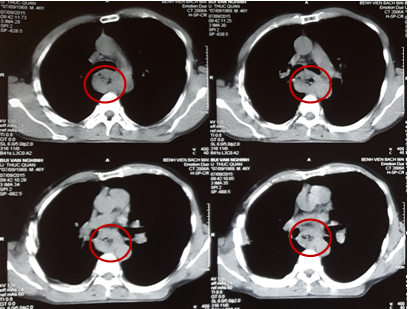

Kết quả chụp cắt lớp vi tính lồng ngực cho thấy: Thực quản đoạn 1/3 giữa dày thành quanh chu vi, không đều, chỗ dày nhất 13 mm, gây hẹp lòng thực quản đoạn dài 50 mm, thâm nhiễm mỡ xung quanh, ôm quanh > ½ chu vi động mạch chủ xuống đoạn ngang mức. Không thấy hình ảnh di căn hạch xung quanh và các cơ quan lân cận.

3010_anh_2.png

Hình 2: Hình ảnh khối u thực quản thâm nhiễm mỡ xung quanh (vòng tròn đỏ)